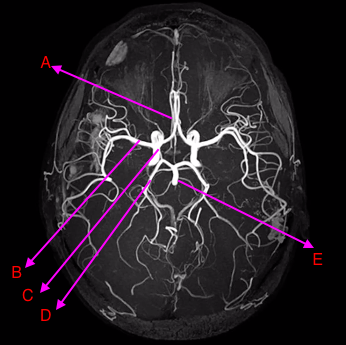

draw the circle of willis xxx

Label A-C

A: anterior cerebral artery

B: middle cererbral artery

C: internal carotid artery

label A-D [4]

A: vertebral artery

B: superior cerebellar artery

C: posterior cerebral artery

D: basilar artery